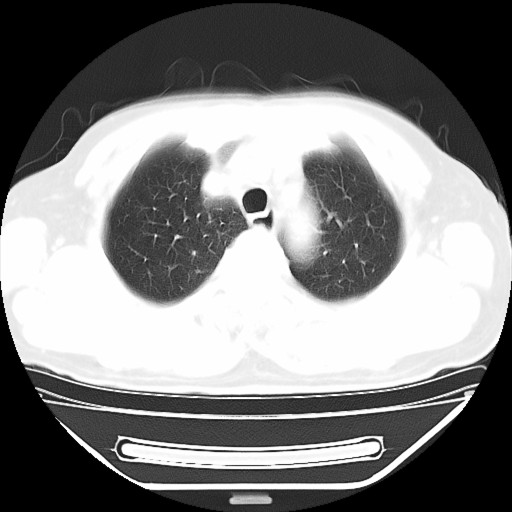

以下是引用hhcckk在2009-5-29 10:34:00的发言:[br]左下肺片絮状边缘模糊影,考虑感染,建议治疗后复查[br]